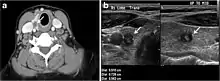

Fig. 1. An incidentally discovered colloid nodule with calcification, shown on CT scan of a 58-year-old female patient. a Non-enhanced axial CT scan of the neck demonstrates a coarse calcification at the left thyroid inferior pole. b Sagittal grey scale ultrasound of the thyroid demonstrates a heterogeneous nodule with a predominant cystic component. Calcification was not seen in the ultrasound, probably due to its lower location in the superior mediastinum.[1]